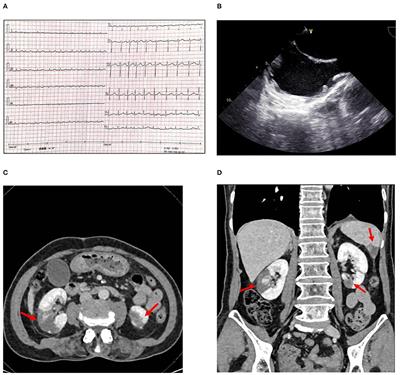

Cancer-associated thoracic aorta arterial thrombosis: case report and review of the literature